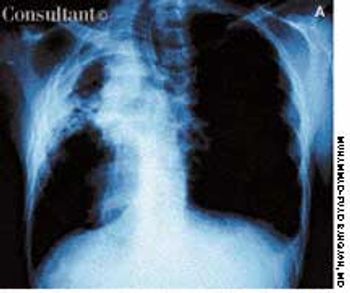

A 41-year-old man with a past history of tuberculosis presented to the emergency department with massive hemoptysis. The patient denied fever or chills but reported a 20-lb weight loss and intermittent hemoptysis during the last 6 months. Six years ago, he had been treated for tuberculosis.